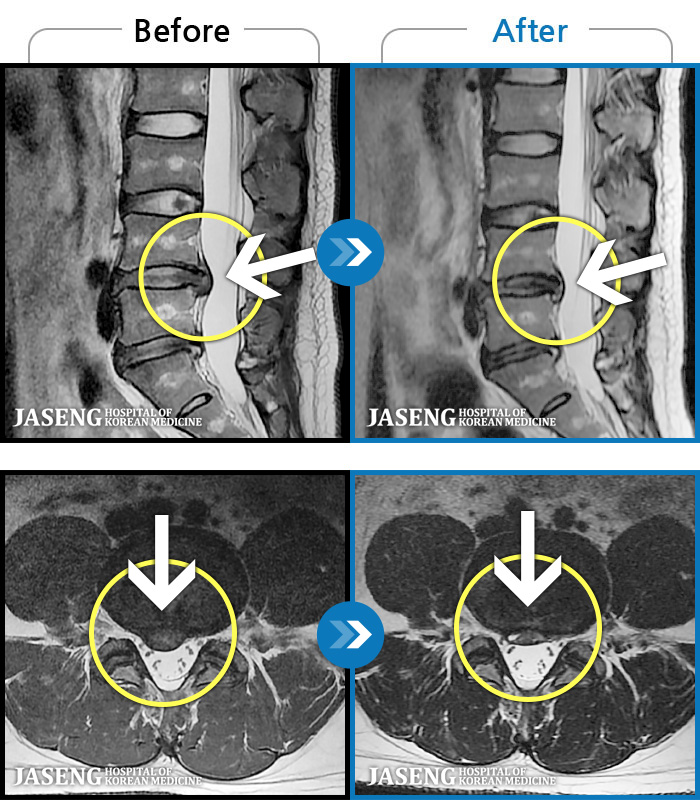

MRI ġ

1,301 MRI ũ ʸ Ȯϼ.